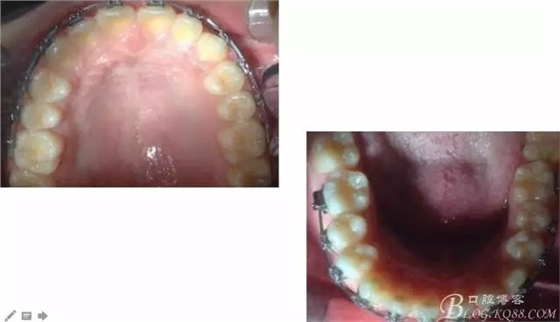

看看口內照吧!真象“大暴牙”v假象“大暴牙”

三度深覆合,三度深覆蓋,尖牙,磨牙均二類關系!